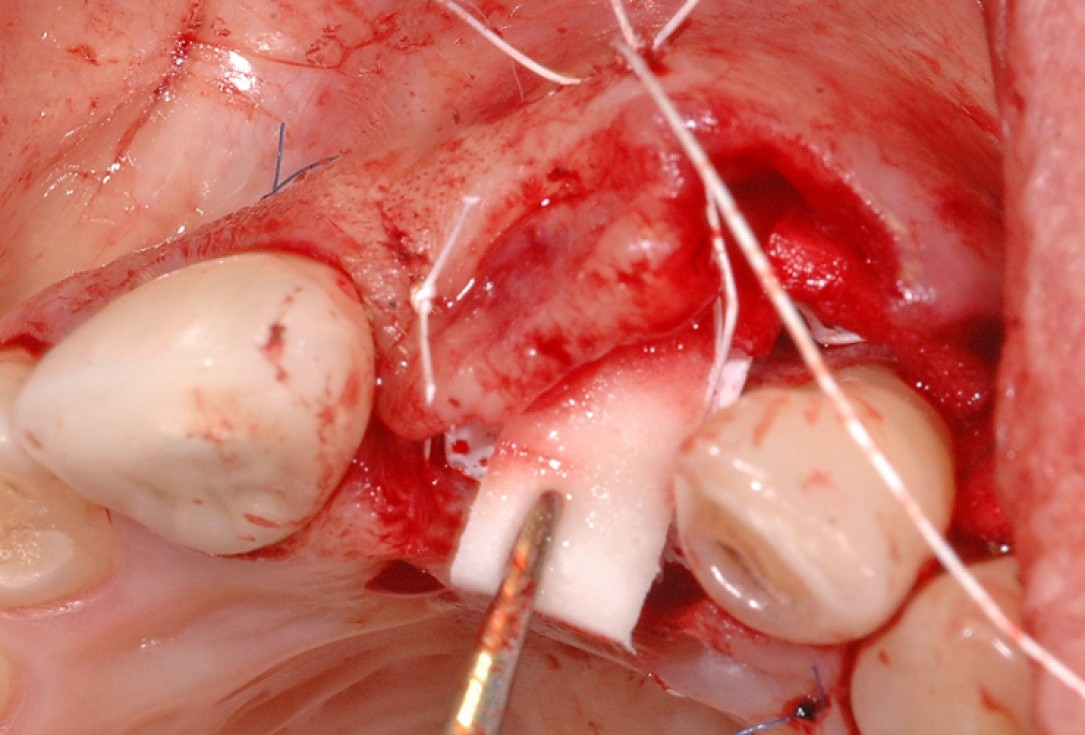

5/18 - Situation after implantation showing a buccal defectGBR together with soft tissue augmentation with mucoderm® and maxresorb® - Dr. S. Scherg